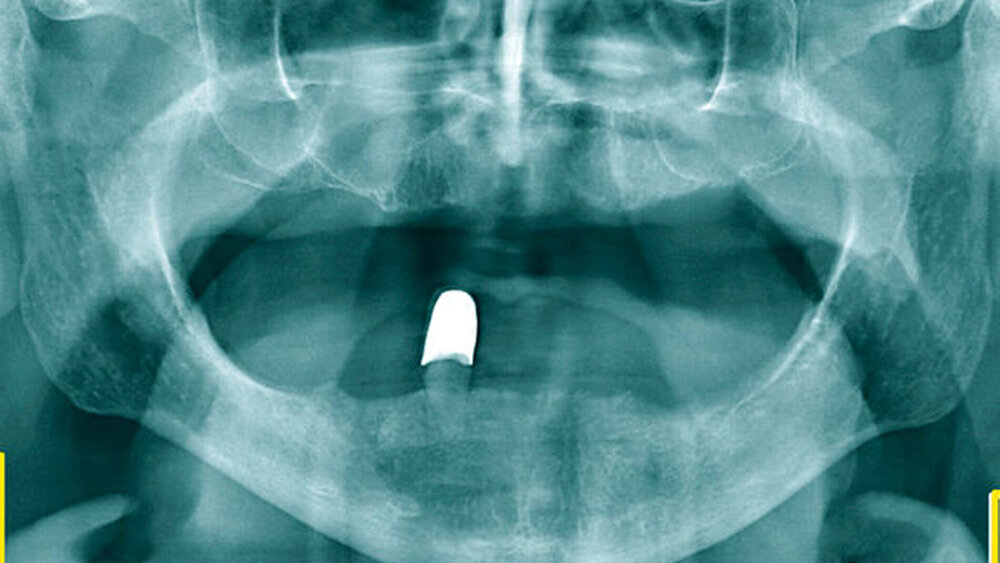

Diese arteriosklerotischen Plaques im Bereich der A. carotis communis sind auf Panoramaschichtaufnahmen mit einer Prävalenz von 2 bis 5,7 Prozent zu finden [Bayer et al., 2011; Sutter et al., 2018; Ribeiro et al., 2018]. Kalzifizierte Plaque bildet sich auf der Panoramaschichtaufnahme meist im Bereich der Carotisgabel auf Höhe der Halswirbel C3, C4 kaudal des Unterkieferwinkels ab. Der Verlauf ist zumeist (röhrenförmig) vertikal und aufgrund der randständigen Lage zur Schicht scharfer Darstellung ergibt sich eine kalkisodense und häufig (je nach Gerät) geringgradig unscharfe Abbildung.